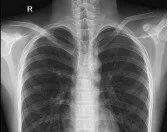

患者韦小弟,因“跌伤致左肩部疼痛2小时”到我院外科住院治疗,入院后经查体,结合检查结果,明确诊断为:左锁骨骨折。

术前拍片

经查体,左肩部可见组织肿胀畸形,可触及左锁骨中端骨折断端阶梯感,压痛明显,纵向叩击痛,左肩关节功能障碍,且家属有手术意愿,为其完善DR拍片、抽血检验等相关术前检查,排除手术禁忌症,经内科、麻醉科等科室会诊后,均认为可择期行手术治疗。手术过程中,医护人员密切配合,麻醉师准确控制麻醉药物的剂量和速度,确保患者在无痛的状态下接受手术。医师团队则凭借精湛的技术和丰富的经验,成功完成了骨折复位内固定手术。